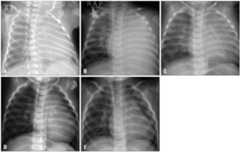

Fig. 1.

Chest roentgenography obtained shortly after premature birth (A), on admission after the onset of shock with cardiomegaly and unilateral white out of entire left lung field (B), and three months after the onset of symptoms checked at out patient clinic in which cardiomegaly renders cardiac sillhouette vague (C), and gradual improvement of cardiomegaly after 6 (D) and 12 months (E).

Two months later at an outpatient follow-up visit, the patient continued to have decreased breath sounds with total haziness of the left lung field on roentgenography, making it difficult to assess the cardiac silhouette and size (Fig. 1 C). Chest computed tomography (CT) (Fig. 3A, B, and C) with 3 dimensional (3D) reconstruction of the airway revealed severe external compression of the left main stem bronchus between the enlarged left atrium and the aorta, resulting in atelectasis in the left lung (Fig. 3 D). As the patient did not show any signs of respiratory distress, she was treated with conservative management. The patient showed normal growth and development without any neurologic complications. With gradual improvement of cardiomegaly and LV function, the atelectasis resolved spontaneously within 2 months (Fig. 1 D and E). After a year of treatment with oral carvedilol, follow-up echocardiography showed normal LV systolic function and nearly normal LV contour (Fig. 4). One year from the onset of symptoms and signs, as an 14 month old female infants, the patient showed normal growth with body weight 11.4 kg (25-50 percentile), height 77 cm (25-50 percentile) and normal development without any neurologic complications. She is now managed at regular follow-up visits and is asymptomatic.